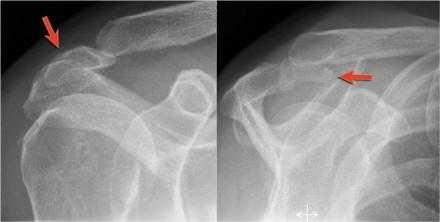

Акромиальная кость

Нарушение одного их центров окостенения акромиона приводит к образованию акромиальной кости.

Определяется в 5 % случаев.

Обычно является сулучайной находкой и относится к нормальным вариантам анатомии.

Однако она может вызывать импинджмент, при нестабильности она може смещатся вниз при отведении дельтовидной мышцы, которая прикрепляется в данной области.

На МРТ изображениях акромиальная кость лучше всего видна на верхних аксиальных изображениях.

Она должна быть отмечена в описательной части, поскольку у пациентов направляемых на подклювовидную декомпрессию резекция акромиона дистальнее синхондроза может в еще больше дестабилизировать синхондроз и привести к гипермобильности после хирургического вмешательства и даже усилить сдавление.

На аксиальном МРТ изображении показана акромиальная кость с дегенеративными изменениями, такими как субхондральные кисты и остеофиты (стрелка).